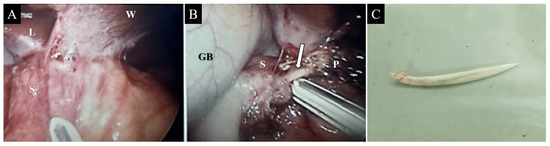

A 49-year-old woman without any underlying conditions presented to our emergency department with worsening dull epigastric pain for over 2 months, general soreness, and fever for 2 days. Physical examination revealed fever up to 39.1 °C with tenderness over the epigastric area; no other complications were reported. Laboratory data indicated a white blood cell count of 8400/µL (neutrophils 88.7%) and a mildly elevated level of C-reactive protein (3.6 mg/dL). The liver function test results and pancreatic enzyme levels were within normal limits. Furthermore, abdominal sonography revealed a small hypoechoic lesion in the hilar area of the liver, and esophagogastroduodenoscopy barely revealed superficial gastritis without mucosal protrusion or ulcer suspiciously indicating the site of foreign body penetration or other etiology. Further investigation was performed through abdominal computed tomography (CT) that revealed a 2.7 cm radiopaque foreign body located between the prepyloric region of the stomach and the pancreatic head and a multiloculated abscess in the pancreatic head and near the aforementioned foreign body (Figure 1). The patient recalled swallowing a piece of fish bone accidentally 2 months prior. Gastric perforation with pancreatic abscess secondary to the fish bone penetration injury was suspected. Considering the length of the fish bone, extraluminal migration, and concurrent multiloculated pancreatic abscess, she was admitted to the hospital and received laparoscopic surgery for removal of the fish bone. The intraoperative findings were a 4 cm long fish bone penetrating through the posterior wall of the gastric antrum into the pancreatic head (Figure 2B,C) and adjoining the pancreatic abscess, and a severe adhesion between the distal stomach and liver, which was identified (Figure 2A) and removed through adhesiolysis. Antibiotic treatment was administered for postoperative symptomatic and supportive treatment. The patient recovered well and was discharged on the seventh postoperative day. No complications were noted in a subsequent health checkup 1 year after the operation.

Figure 2. Laparoscopic view displaying severe adhesion between the distal stomach and liver (A). A linear and hard foreign body (arrow) was observed between the gastric antrum and the pancreatic head (B). The removed foreign body measured 4 cm in length and resembled a fish bone (C). Note—L = liver; S = stomach; W = abdominal wall; GB = gallbladder; P = pancreas.